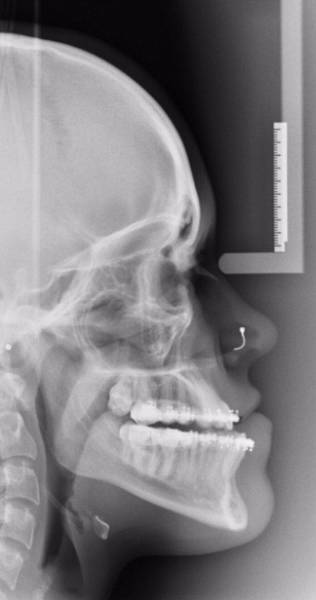

Loulou Rich oli koulukiusattu nuori tyttö, häntä haukuttiin ”pilalle menneeksi naamaksi” – tämä johtui poikkeuksellisen vahvasta alapurennasta, koska hänen leukansa oli jopa 8 millimetriä liian edessä. Loulou kärsi vakavista itsetunto-ongelmista ja hän yritti peittää kasvonsa valokuvissa. Hän käytti apunaan meikkiä, jolla leuan sai meikattua ”piiloon.”Raudat ja leikkaus auttoivat

Louloulla oli kolmen vuoden ajan raudat, jonka jälkeen hän oli valmis leikkaukseen. Plastiikkakirurgi leikkasi Richin leukaa 4 tunnin ajan ja samalla ylä- ja alaleuka asetettiin samalle tasolle. Nyt hänen hymynsä on suorastaan lumoava ja kaikki kiusaajat katuvat taatusti tekojaan.#1